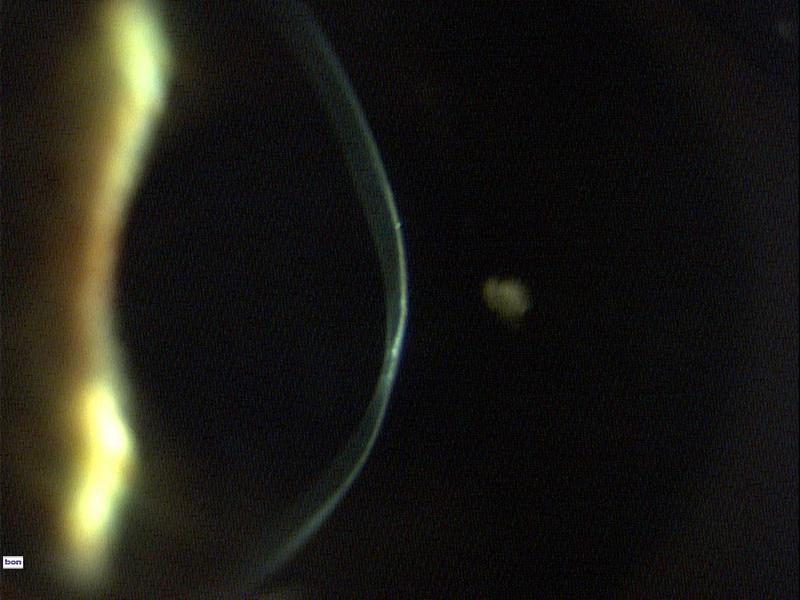

Da die Hornhaut bei diesem Linsentyp vollständig überbrückt wird, bietet sich diese Korrekturmöglichkeit bei unregelmäßiger Hornhaut, wie z.B. bei Keratokonus, Hornhautverletzung und Hornhauttransplantation an. Durch die geringe Beweglichkeit der Linse, wird diese von den Trägern spontan als komfortabel empfunden. Der Vorteil liegt in der stark verbesserten Sehleistung. Die Tränenflüssigkeit zwischen der Linse und der Hornhaut gleicht die Hornhautunregelmässigkeit aus.

Sklerallinse bei Keratokonus Sklerallinse bei Keratokonus_Bild: Gustav Pöltner "Speziallinsen-Guru"